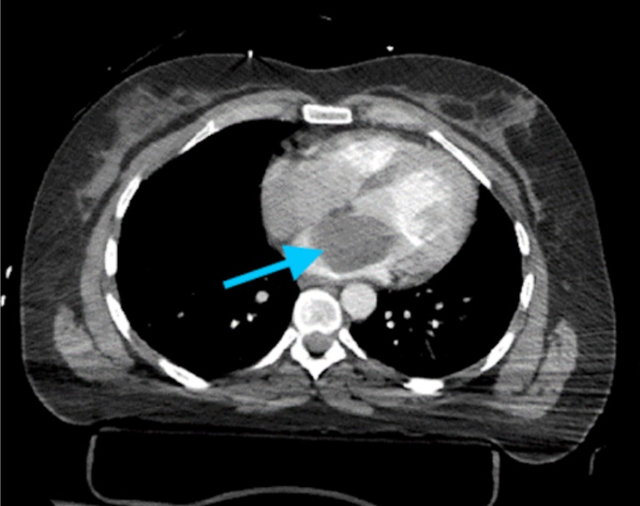

Bạn đã từng nghe đến u nhầy ở tim chưa? Đây là một loại u lành tính khá hiếm gặp. Loại u này thường phát triển ở tâm nhĩ trái và có thể gây ra các biến chứng nghiêm trọng nếu không được phát hiện và điều trị kịp thời.

Các khối u ở tim có thể xuất hiện ở bất kỳ mô tim nào. Khối u tim có thể là nguyên phát hoặc di căn. Điều trị các khối u lành tính bằng phẫu thuật cắt bỏ, tuy nhiên khối u có thể tái phát. Điều trị ung thư di căn phụ thuộc vào loại và nguồn gốc khối u, tiên lượng bệnh thường rất xấu.